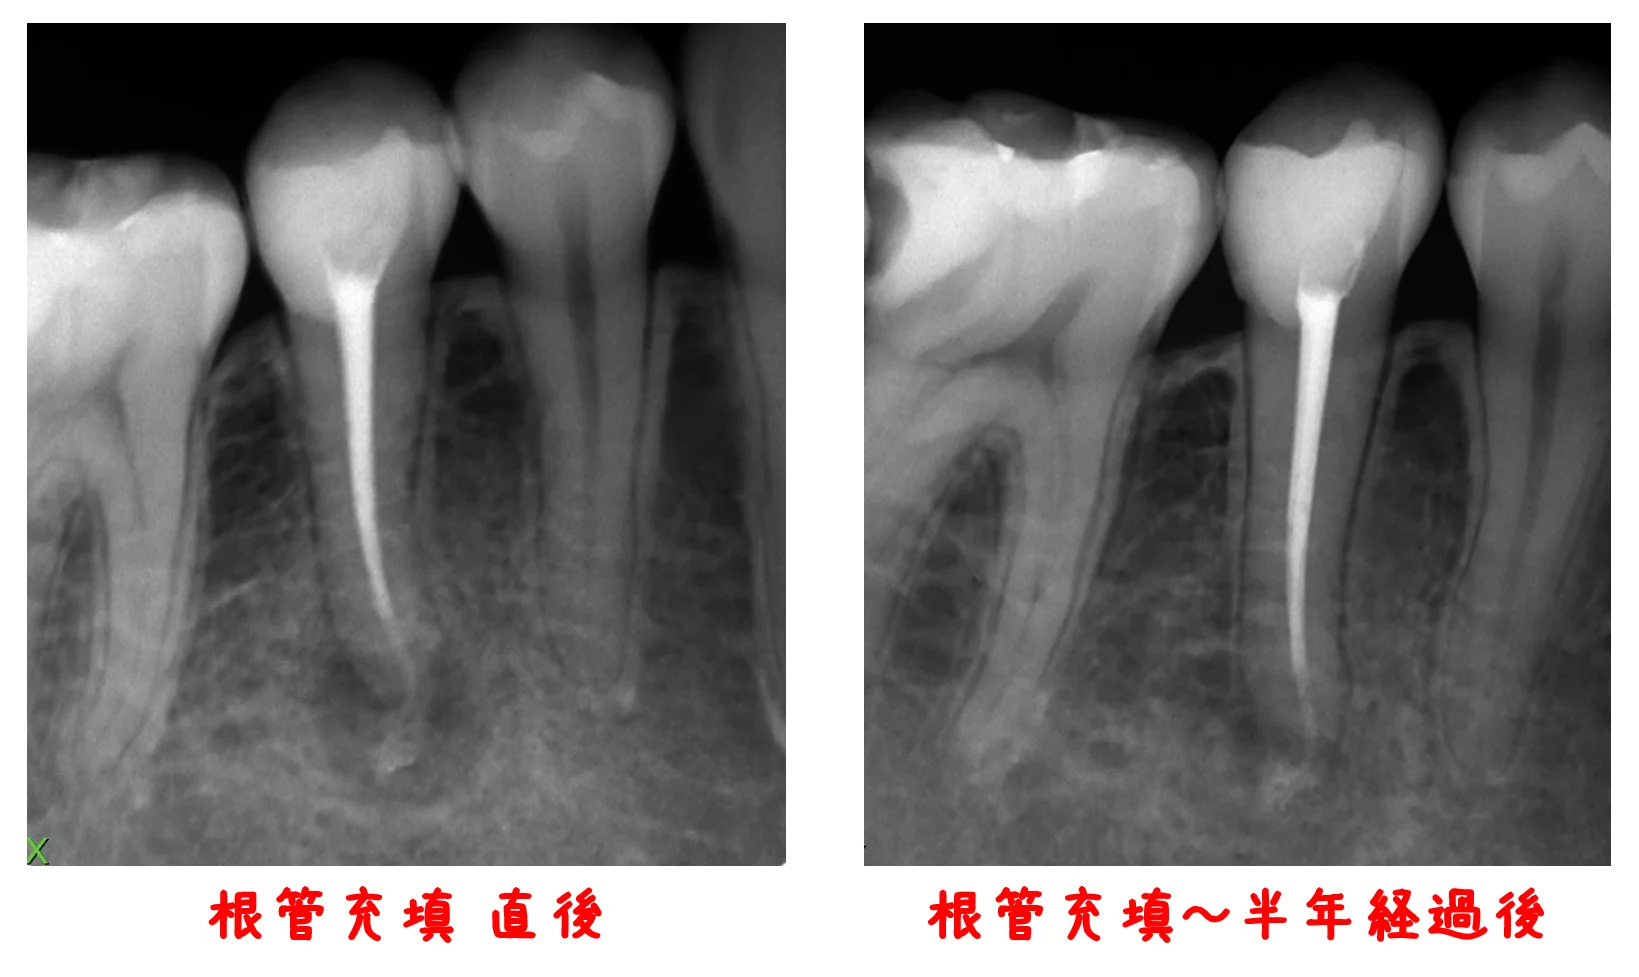

神経の治療④

こんにちは。 昨日は茨城県南歯科医師会の新年会に参加してきました。 久々にお会いする先生方とも色々な話が出来、非常に楽しかったです。 さて、今回は前回の「神経の治療③(リンクが開きます)」でお見せした患者さんの根管充填を行ってから半年が経過…

続きを読む →